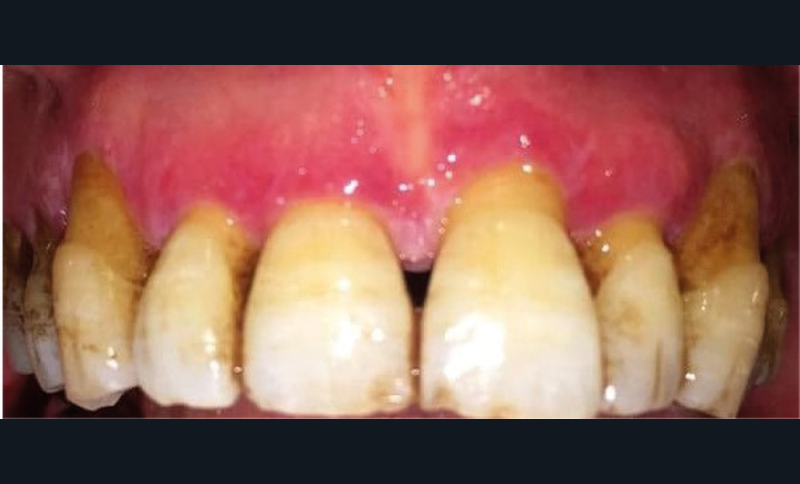

À l’interrogatoire, le patient affirme qu’il a des difficultés à maintenir une hygiène bucco-dentaire satisfaisante du fait des douleurs, et n’a pas pu consulter son chirurgien-dentiste pour son détartrage annuel en raison de la crise sanitaire en cours. L’examen clinique révèle une parodontite chronique (stade 3) généralisée et des lésions jugales (fig. 1 et 2), labiales (fig. 3) et gingivales (fig. 4) érythémateuses et kératosiques. Les lésions kératosiques jugales sont de type réticulé (fig. 1 et 2) ; les lésions kératosiques labiales sont associées à de petites érosions (fig. 3) ; les lésions palatines à des ulcérations (fig. 5). La langue présente une lésion blanche en « tache de bougie » (fig. 6) ; la muqueuse du plancher buccale est saine (fig. 7). Le signe de la pince est négatif. Le patient n’est pas porteur de prothèse dentaire malgré un édentement de moyenne étendue. Aucune lésion cutanée ou génitale n’est rapportée par le patient.